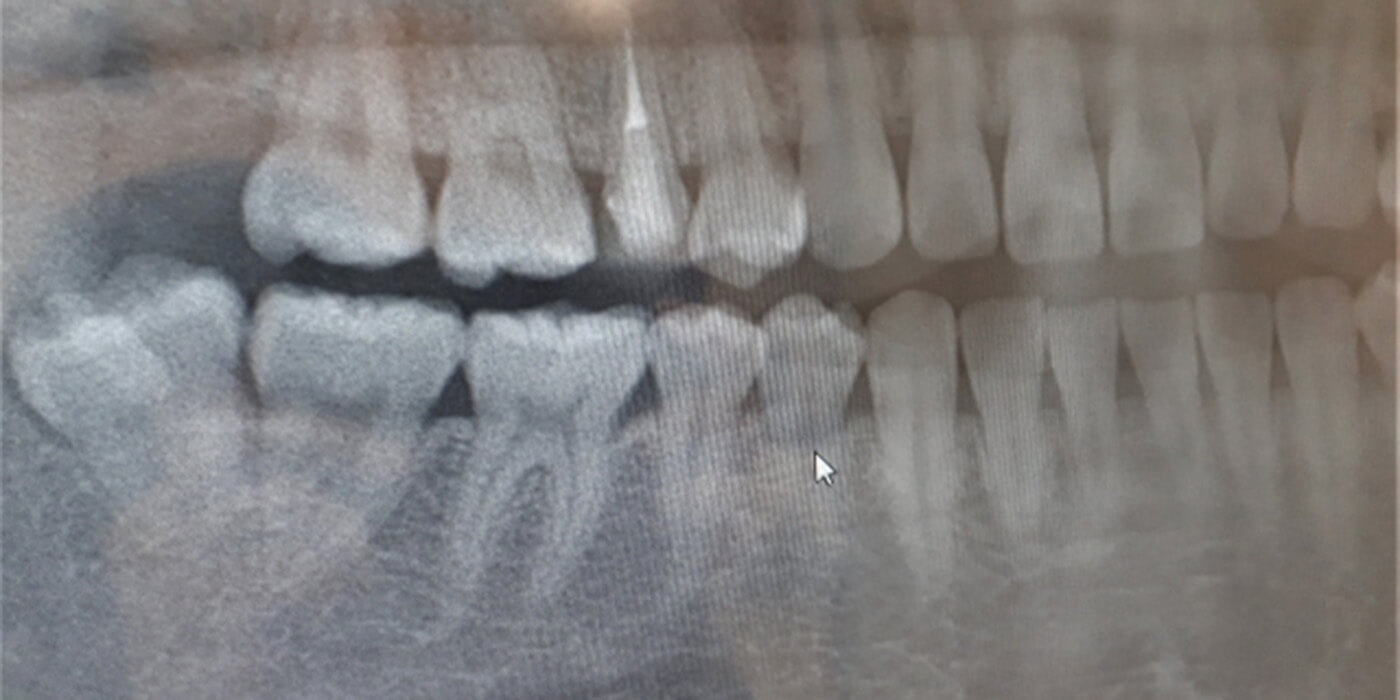

「親知らず」は一番最後に生えてくる(18~20歳くらいに生えます)ため、生える場所が残されていません。骨の中に埋まったまま出てこなかったり、横や斜めに生えてきたりすることが多く、完全な形で生えてくる人は稀です。

横や斜めに生えてきた状態のままになったりすると、歯ブラシをしても手入れがしにくく、汚れがたまりやすく、そのためにむし歯になり痛んだり腫れたりすることが多いです。